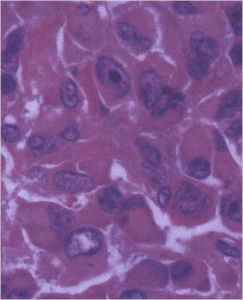

- They have a similar appearance microscopically as a conventional osteoblastoma except the osteoblasts are twice as large and have an epithelioid quality with abundant eosinophilic cytoplasm (Epithelioid Osteoblasts).

- Aggressive osteoblastoma is a borderline lesion lesion between osteoblastoma and osteosarcoma. It is not a precursor to osteosarcoma. It does not metastasize.

The differential between osteoid osteoma, conventional osteoblastoma and aggressive osteoblastoma is based on size and the presence of epithelioid osteoblasts. Can have epithelioid osteoblasts in osteoid osteoma and conventional osteoblastoma but they do not occur in cohesive sheets that fill intertrabecular spaces